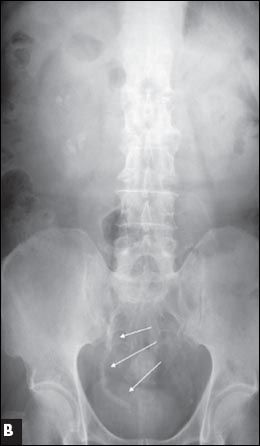

Figure 2 – A large right upper caliceal renal stone is shown on a pretreatment radiograph (

A

). After one session of extracorporeal shockwave lithotripsy, stone fragments are scattered inside the mid and lower calices and steinstrasse formation is evident in the right lower ureter (

B

, arrows).

Extracorporeal shockwave lithotripsy. Since its introduction in 1980, ESWL has become a common first-line treatment option for urinary stones, especially those smaller than 1 cm. The success rate is lower for large renal stones. There is a higher risk of obstruction because of the production of a large amount of small stone fragments or steinstrasse (stone street) (Figure 2). For stones larger than 2 cm, PCNL is a better option.